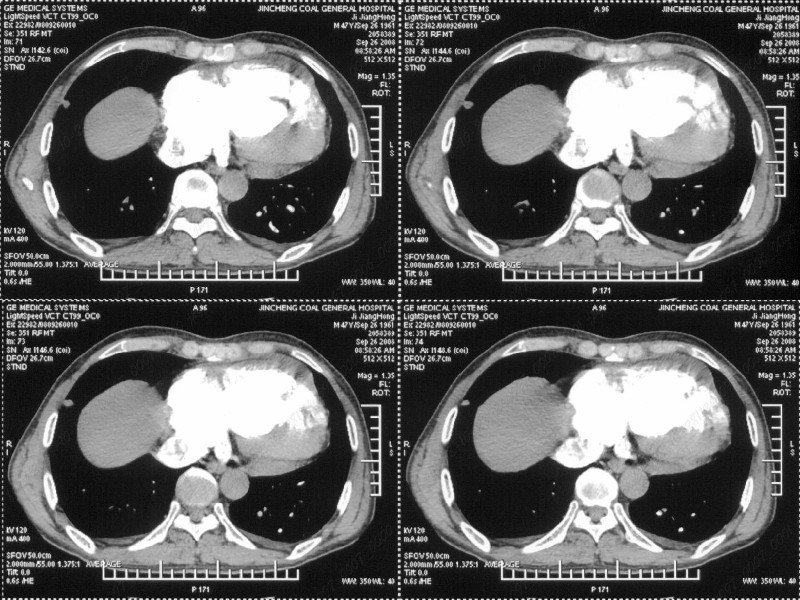

男性,47岁。胸部不适一年,ct检查发现右胸膜下结节。http://www.radida.com/bbs/forum.php?mod=viewthread&tid=46094

图像很清,资料很全。工作做的很细,向您学习!观阁下的强化图像发现,您们强化后扫描时间挺早,延迟时间大约在16—18秒之间吧。估计目的是为了观察肺动脉及分支的情况。但现有的资料并不能提示动脉栓塞改变。建议楼主可在机器上仔细观察,或许会有异常发现。另外,个人感觉右侧应为肺内结节而非胸膜结节。考虑肺内良性小结节,炎性假瘤可能性大。

右下肺前胸膜下小结节,强化不明显。建议定期观察!

病灶周围似有纤维化征像,增强明显强化,但中央可见点状低强化区,考虑慢性病变可能如炎性假瘤等,病灶边缘部分毛糙有切迹,双侧胸腔少量积液影,不除外恶性

结节未见明显强化,局部胸膜增后粘连,内缘纹理影增重伴小围星灶,局部胸膜下小三角状实变影,尖端见纤维索牵扯征,综合考虑炎性病变,有增殖表现,不出外tb灶

右肺中叶外侧段胸膜下结节状病灶,性质待定(不排除周围型肺癌可能)。

小结节的周围似乎与斜裂的走行有关,边缘分界不很清楚,与侧胸膜关系密切,有轻度强化,不能除外恶性,建议密切观察。

汇报临床诊断:右肺动脉分枝栓塞

右肺静脉充盈缺损,左心房体积小,右肺动脉远端动脉充盈缺损,右肺血管影细小,考虑;右肺动脉远端栓塞.